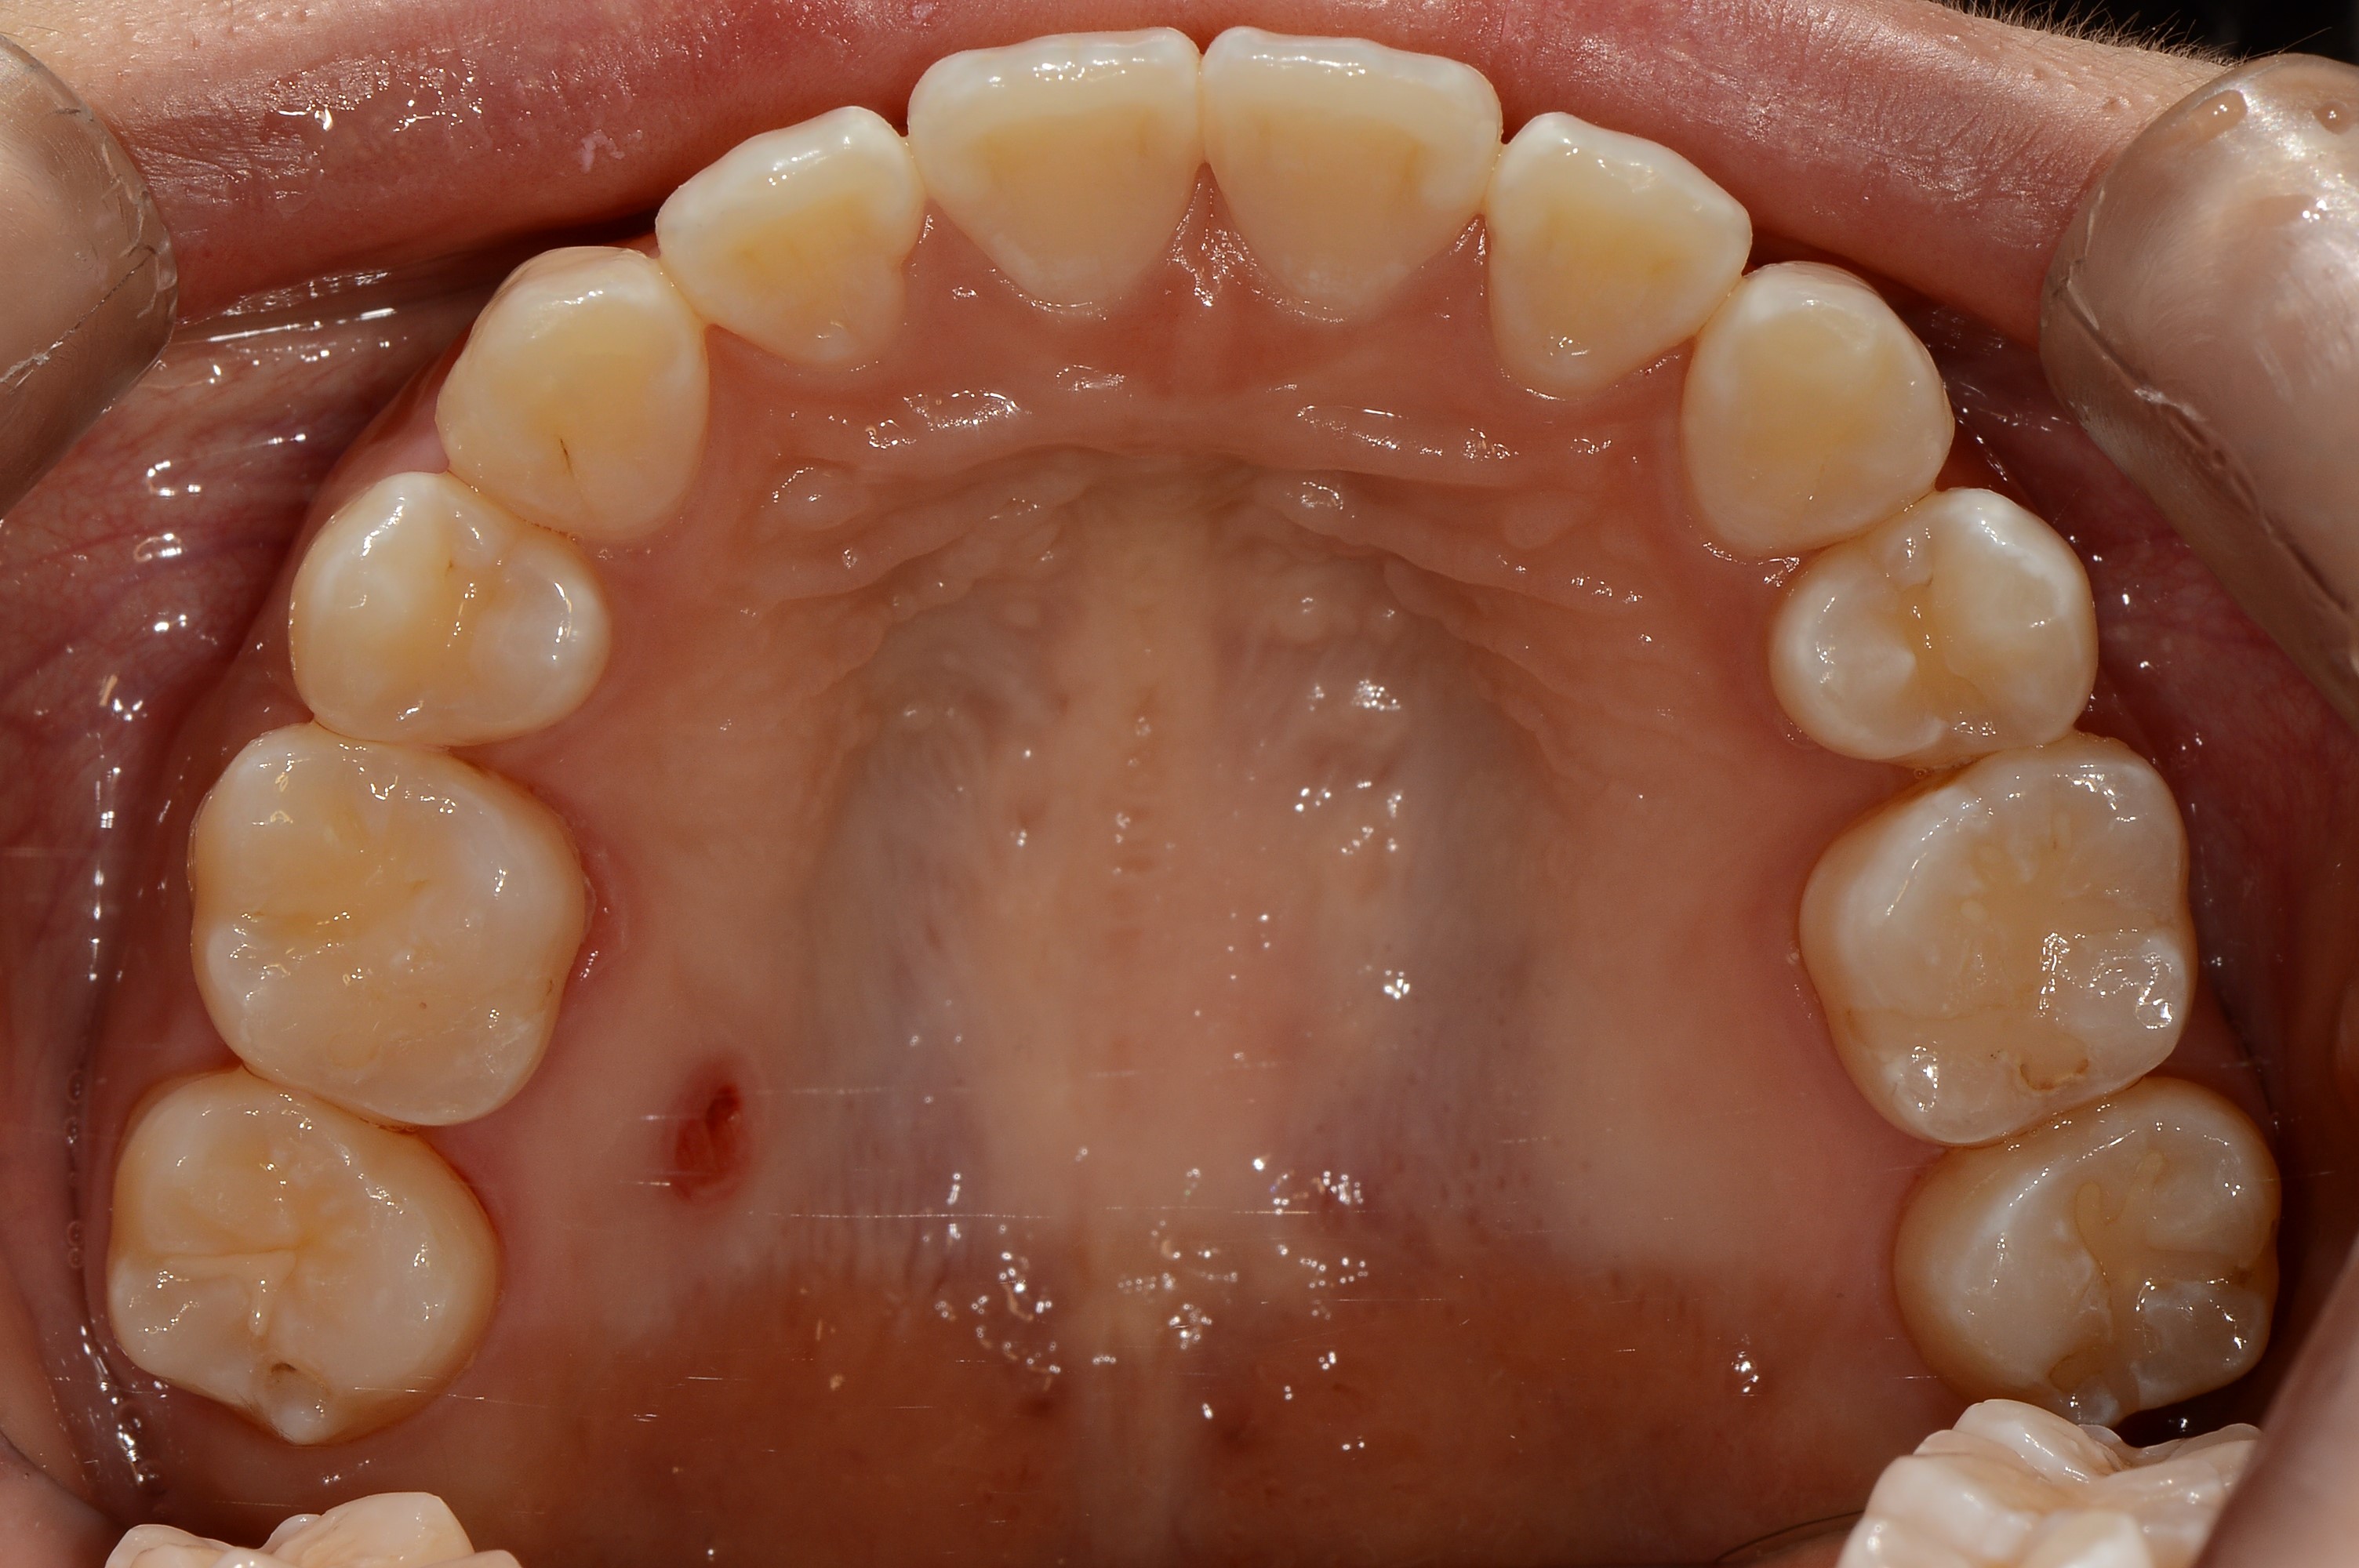

치료 전 사진입니다.